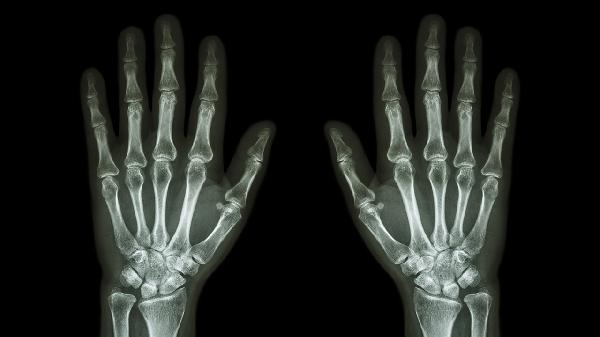

中老年人群因关节软骨退化,长期手机操作可能加速小拇指掌指关节磨损。晨起关节僵硬明显,X线可见骨赘形成。建议减少机械性刺激,补充硫酸氨基葡萄糖胶囊,疼痛严重时短期使用洛索洛芬钠片。关节腔注射玻璃酸钠需由专科医生评估。